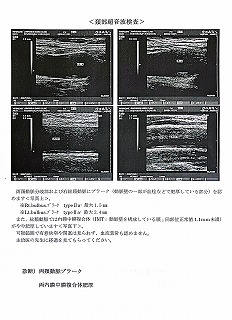

090 脳ドック

2024.18.14 荒尾市民病院 2023.08.10 荒尾市民病院

2024 PDF 2023 PDF